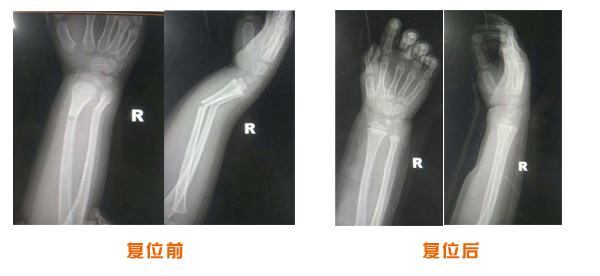

復位前后對比

尺橈骨克雷氏骨折治療前后